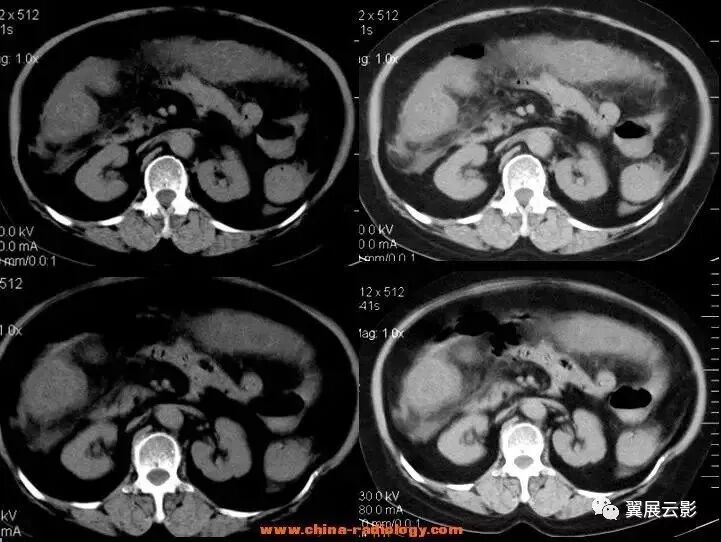

下图肠扭转病例:

下图是闭襻性的肠梗阻

闭袢型肠梗阻